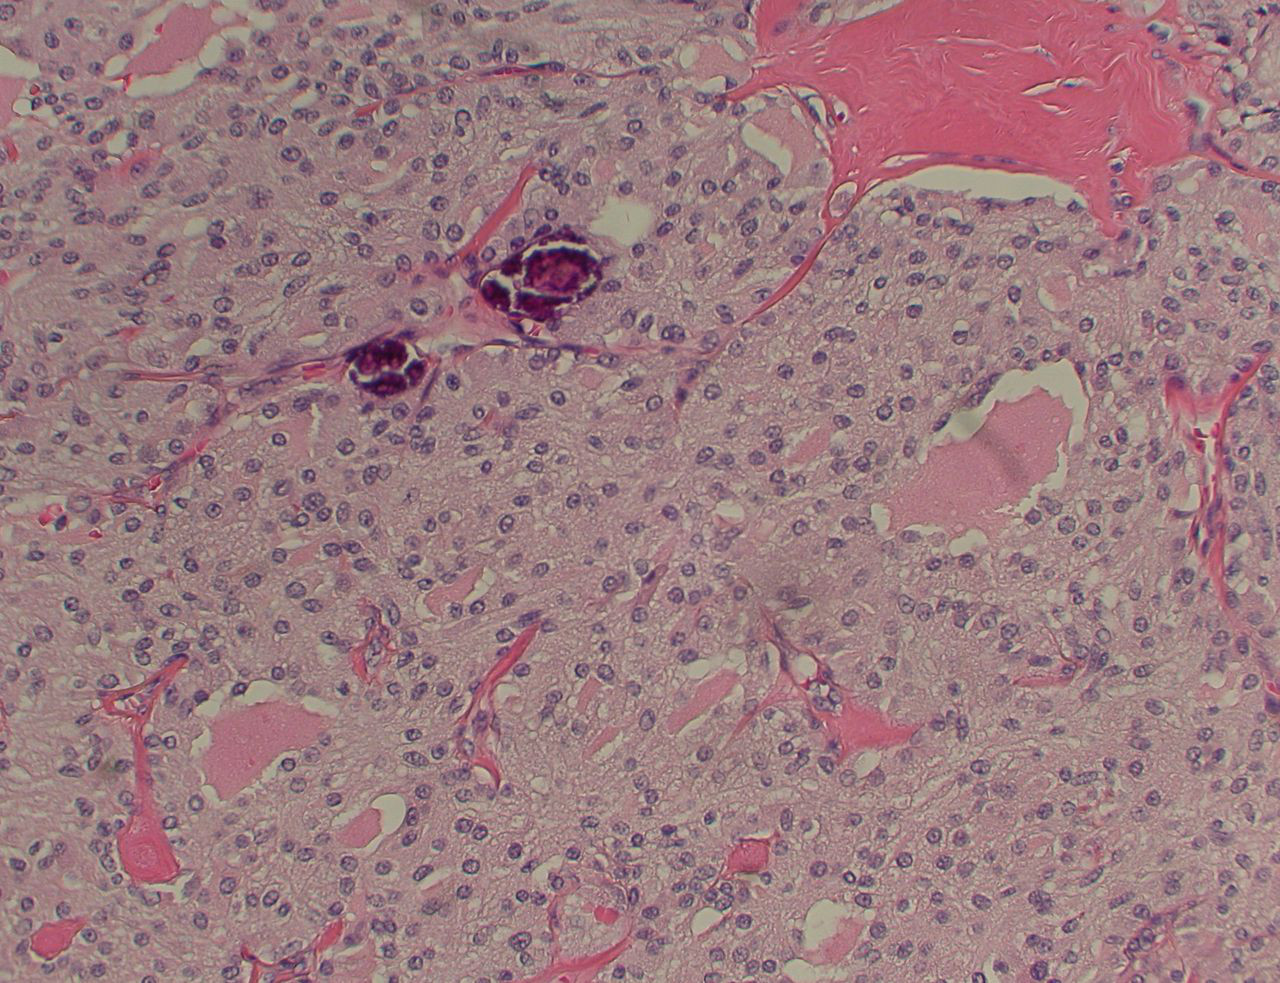

Medullary thyroid cancer: H&E stain showing nests of tumour cells

Mohan V et al. BMJ Case Reports CP 2019;12:e230446; used with permission

See this image in context in the following section/s: